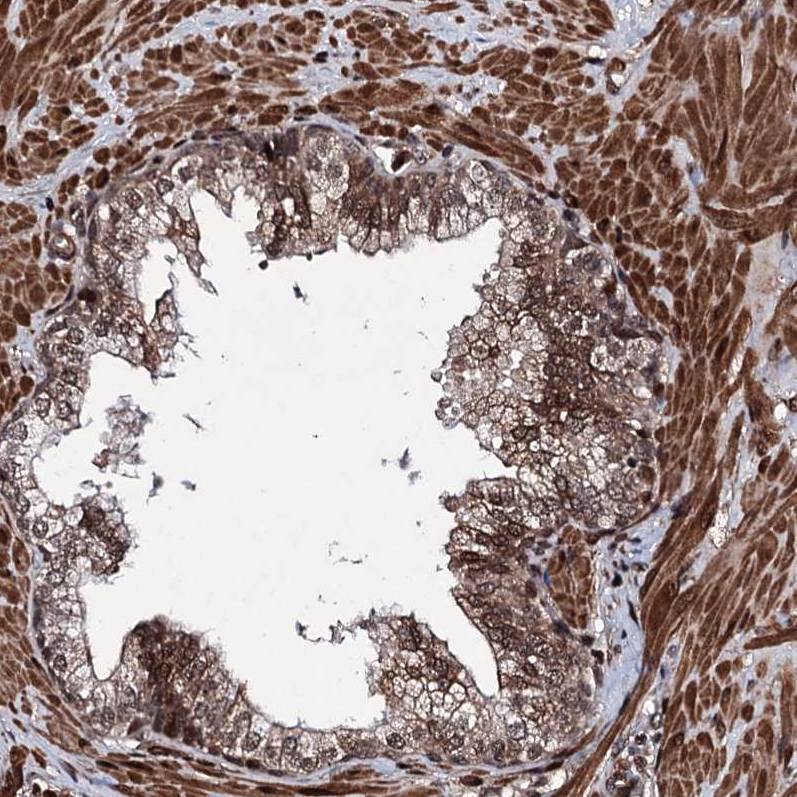

Immunohistochemical staining of human fallopian tube shows strong nuclear positivity in glandular cells.